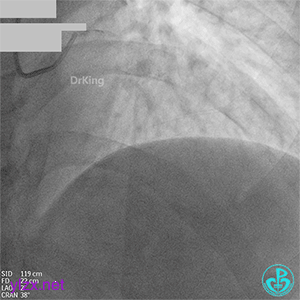

08 1个月后复查

RCA粗大全程瘤样扩张明显,自近段闭塞,TIMI血流0级;可见自身桥侧支逆供RCA远段。

LM未见明显狭窄,LAD开口至近段明显瘤样扩张,自近段闭塞,TIMI血流0级,D1瘤样扩张,TIMI血流2级;可见D1逆供LAD中远段及RCA中远段。

LCX发育小,内膜不光滑,TIMI血流3-级,逆供RCA中远段。